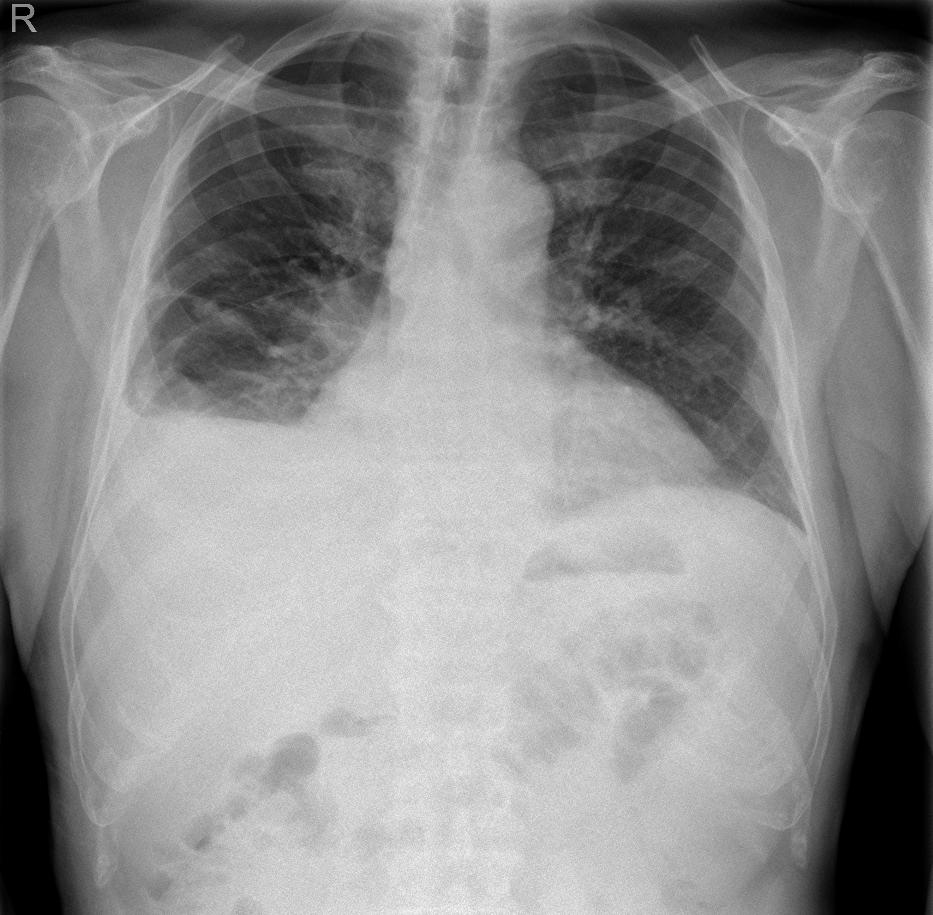

Pacient s adenokarcinomem pravého dolního laloku s metastázou do plic, na RTG hrudníku fluidothorax vpravo.

Ultrazvukovým vyšetřením potvrzen hyperechogenní fluidothorax vpravo, provedena pleurální punkce, získán slámově žlutý výpotek, biochemicky exudát, cytologicky bez maligních buněk.